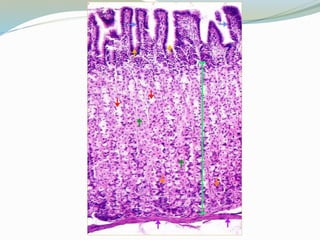

 Epitelio:

 Células cilíndricas

 Células de Paneth

 Células caliciformes

 Células enteroendócrinas

ID: Células cilíndricas

 Cada célula tiene un borde en cepillo

 Borde PAS positivo en relación con el Glucocáliz

 El glucocáliz es resistente a los proteolíticos y

mucolíticos

 Las microvellosidades tienen un centro con filamentos

finos de actina que se mezclan con el velo terminal que

tiene miosina

 Absorben azúcares y aminoácidos por un proceso

activo y pasan al espacio extracelular por difusión

pasiva

Células indiferenciadas

 Fuente de origen de las demás células

 Tienen características de células inmaduras

 Sufren mitosis frecuentes

Células mucosas

 Están dispersas entre las células cilíndricas y su

número aumenta del duodeno a la porción terminal

del íleon

 El moco excretado es una glucoproteína ácida y forma

una película protectora sobre el glucocáliz de las

microvellosidades

Células enteroendócrinas

 Se encuentran en las criptas y vellosidades

 Secretan péptidos reguladores activos que participan

en la secreción gástrica, la motilidad intestinal, la

secreción pancreática y la contracción de la vesícula

biliar

Otros tipos de células epiteliales

 Las células caveoladas no son frecuentes pero se

encuentran en criptas y vellosidades de intestino

delgado, intestino grueso, estómago

 Células migratorias: Linfocitos